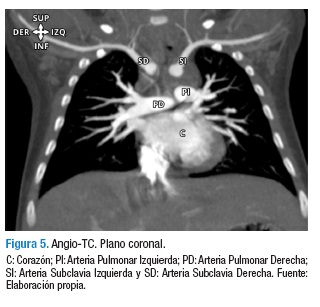

En la Figura 3 se puede observar que el arco izquierdo fue de mayor tamaño que su contra lateral; ambos arcos proveen bilateralmente dos troncos arteriales principales, los dorsales correspondientes a las arterias subclavias y los ventrales a las arterias carótidas comunes, Figuras 4 y 5; dichos vasos se opacificaron adecuadamente con medio de contraste y preservaron su calibre y recorrido normales, sin definirse dilataciones o estenosis patológicas, los dos arcos aórticos generaron morfología en anillo alrededor de la tráquea y el esófago con compresión sobre dichas estructuras. Figuras 1 y 3.

La angio-TC y la angioresonancia magnética (angio-RM) son los mejores estudios de imágenes para el diagnóstico y caracterización de los anillos vasculares, dado que proporcionan información completa del patrón de ramificación arterial y evidencian claramente las ubicaciones, tanto del alcance de las vías respiratorias como de la obstrucción esofágica. Además, permiten realizar un diagnóstico diferencial con otras causas de compresión traqueal extrínseca como tumores del mediastino, quistes broncogénicos, hemangiomas, entre otros (17). Incluso, la reconstrucción tridimensional de la arteria aorta y de la vía respiratoria en las imágenes tomográficas puede ser una herramienta útil para la planificación preoperatoria.

Finalmente, cabe resaltar la utilidad de las imágenes de angio-TC y angio-RM como herramientas significativas en la confirmación del diagnóstico y planificación preoperatoria, dado que permiten establecer el diagnóstico definitivo de anillo vascular y sus relaciones anatómicas exactas.